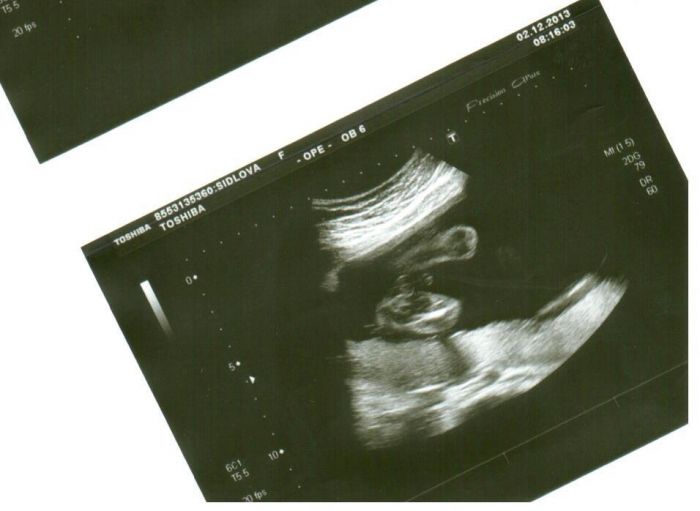

Autor: shidlinka 23.12.2013 v 09:03